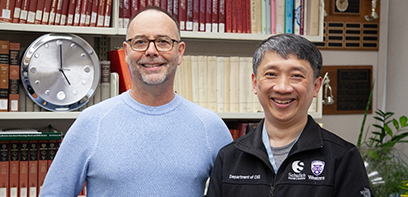

In a Canadian first, surgical team at London Health Sciences Centre performs robotic assisted spinal surgery

The team, led by Schulich Medicine & Dentistry’s Dr. Victor Yang, completed a successful, robotic-assisted direct lateral spine surgery.